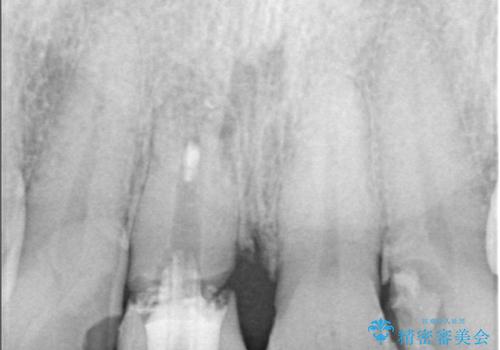

- 右上の前歯(1番)が折れたことを主訴に来院されました。診察とレントゲン検査の結果、歯冠の大部分が失われ、歯根の先には根尖病変(膿の袋)も認められました。残存歯質がほとんどなく、歯を保存することが困難と判断し、抜歯が必要と診断しました。

治療は、まず感染の原因となっていた前歯を慎重に抜歯し、抜歯と同時にインプラントを埋入しました。審美性を重視する部位であるため、骨や歯ぐきのボリュームを維持するための補填処置も併用しています。術後は仮歯を装着し、見た目を保ちながらインプラントと骨がしっかりと結合するのを待ちました。